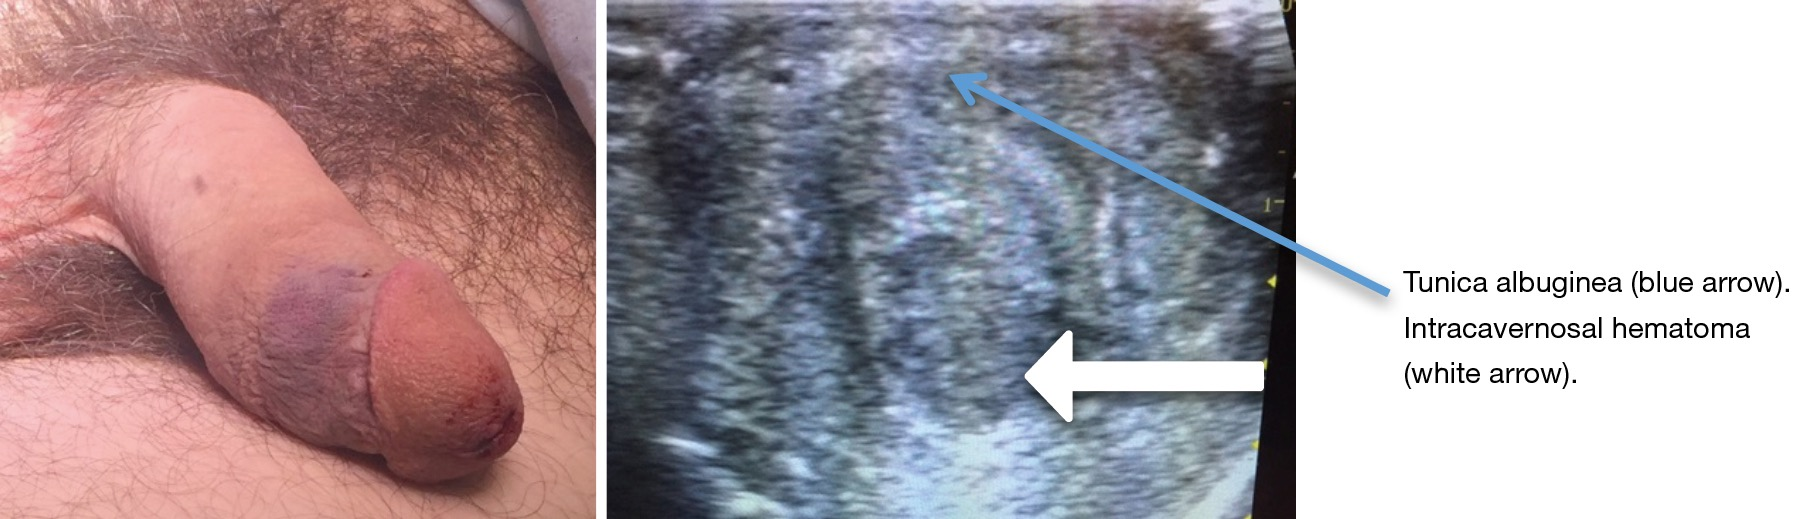

Suspected Penile Fracture To Operate Or Not To Operate Metzler Translational Andrology And Urology